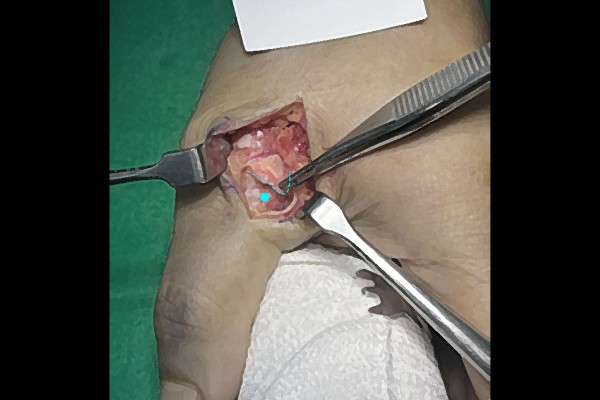

끊어진 인대가 확인됩니다.

끊어진 인대를 수술 도구로 끄집어 내어 뼈에 부착을 해야합니다.